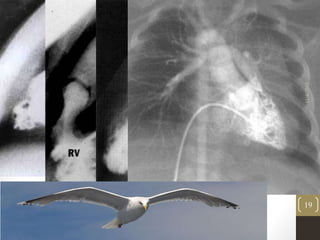

11/4/2015

19

• MC form – valve is dome shaped,2-4 raphes present but no separation

into valve leaflets.

• Trileaflet dysplastic myxomatous valve stenosis (15%) , they have no

commissural fusion.

• Valve annulus hypoplasia

• Commonly seen in patients with Noonan’s syndrome.

• Secondary changes are – RVH,TR and RV failure.

• Post stentotic dilation is usually seen in MPA –can extend into LPA.